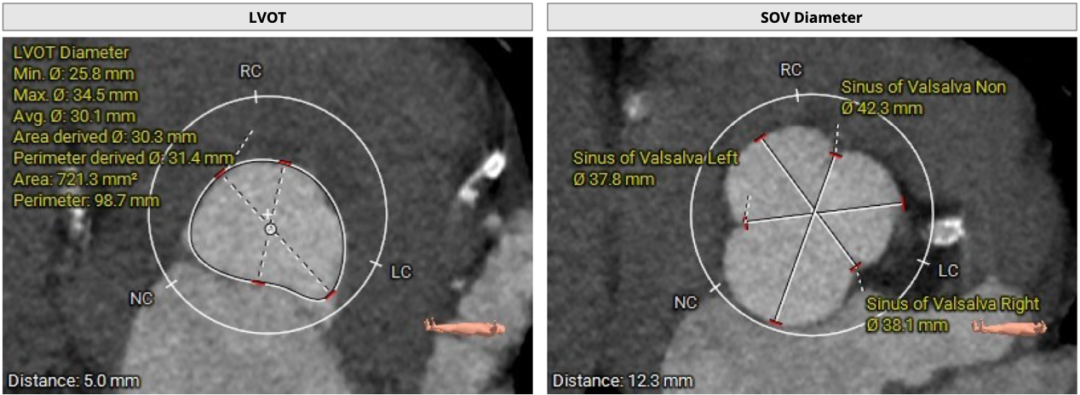

双侧冠脉开口高度可LCA:14.5mm, RCA:22.9mm;右冠轻度钙化,左冠及分支中度钙化: